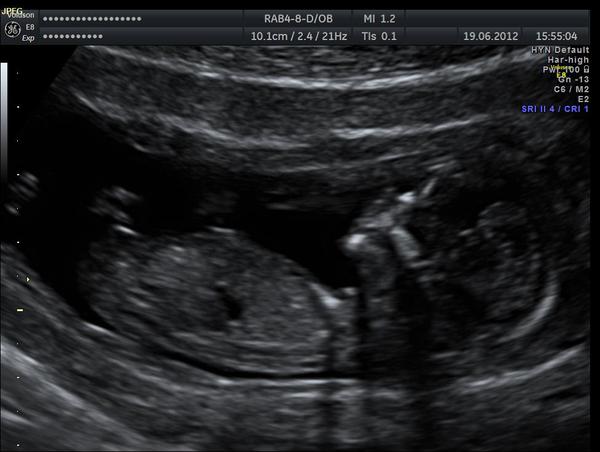

tak a ja hlasim po screeningu ze je vsechno ok, mimi je o tyden vetsi, riziko Downa relativne slusne, druhy TP 20.12 🙂 tak se mi hezky ulevilo, ufff 🙂 snad bude na obrazku neco videt.